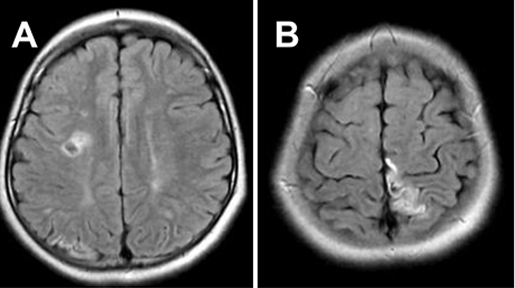

8歲的太一因為右腿運動無力就醫(yī),磁共振血管造影(MRA)顯示雙側(cè)腦梗死,在 Willis 環(huán)周圍分層雙側(cè)血管狹窄閉塞,確診為煙霧病。

患者初次就診時進行的MRA

搭橋術后患者康復,沒有明顯的殘疾。然而,在手術復查和基因診斷后5年,他出現(xiàn)了短暫性腦缺血發(fā)作,伴有反復的左偏癱。MRA 顯示大腦中前動脈的缺損和大腦后動脈的進行性狹窄(圖G 、H)。

圖G&H:發(fā)病5年后進行的MRA顯示主要顱內(nèi)動脈狹窄的顯著進展。